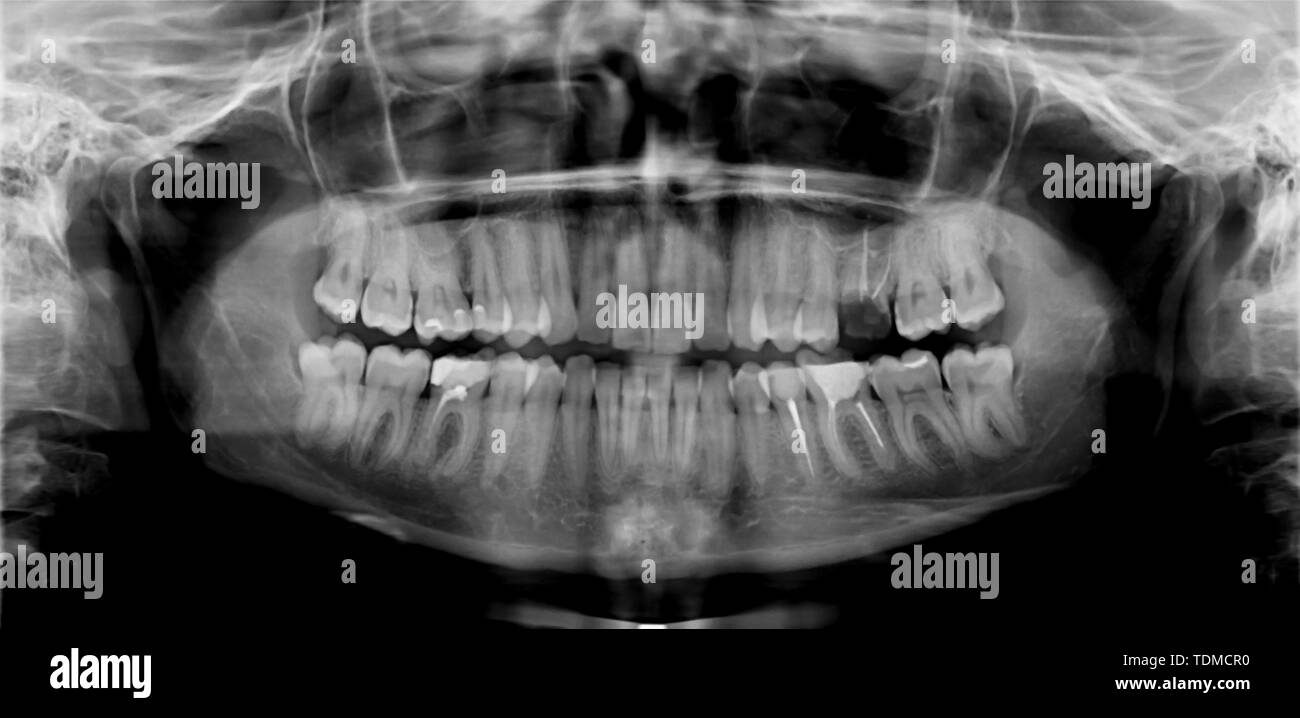

Panoramic dental and mandible xray image Stock Photo Alamy Mandible X Ray Factor — radiography represents the first level imaging technique in patients with traumatic injury of the mandible. Mandibular fractures represent two thirds of all. Mandibular rami and lateral portion of body. — key points. this program of normal radiographic anatomy of mandibular and maxillary periapical projections was originally created by the school of dentistry at the. 4 views. Mandible X Ray Factor.

Panoramic Dental Mandible Xray Image Stock Photo 472503424 Shutterstock Mandible X Ray Factor Mandibular rami and lateral portion of body. this case is an example of a normal mandible series comprising the anteroposterior axial (towne) and bilateral. — radiography represents the first level imaging technique in patients with traumatic injury of the mandible. Mandibular fractures represent two thirds of all. 4 views • pa • towne • lateral obliques. this. Mandible X Ray Factor.